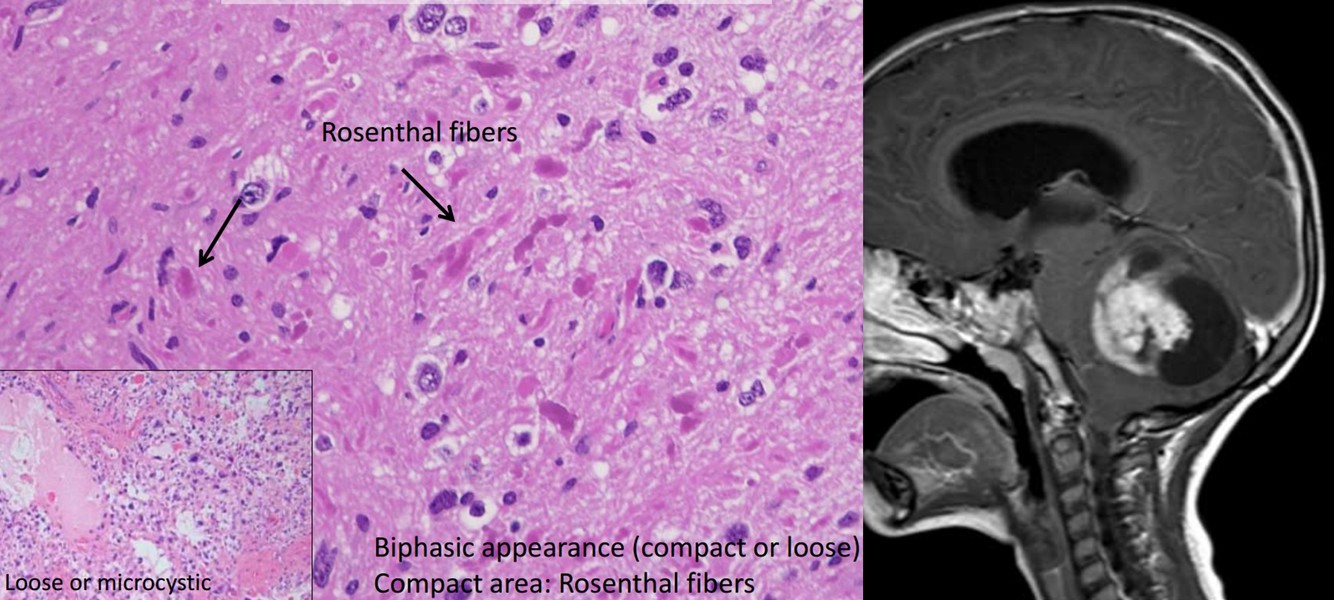

Non-infiltrating Astrocytomas

- Pilocytic astrocytoma

- Grade

- Age

- Location

- Genetics

Non-infiltrating Astrocytomas

- Pilocytic astrocytoma

- Grade I

- Children and young adult

- Cerebellum, thalamus, optic nerve

- NF1

Pilocytic astrocytomas, WHO Grade I

- Biphasic appearance (compact or loose)

- Compact area: Rosenthal fibers

- Age

- Location

- Interval to anaplastic progression